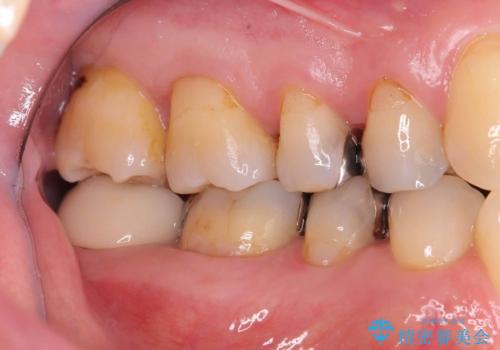

銀歯の下の虫歯|オールセラミッククラウン

- メンテナンスで虫歯が見つかり、治療を行いました。

まず既存の銀歯を除去し、虫歯を取り除いた後、オールセラミッククラウンで修復しました。

銀歯の下は、目に見えないうちに虫歯が進行していることがよくあります。

特に古くなった銀歯や、咬み合わせの圧力で微細な隙間ができた場合にリスクが高くなります。

見た目ではほとんどわからず、定期検診で発見されるケースが多いです。